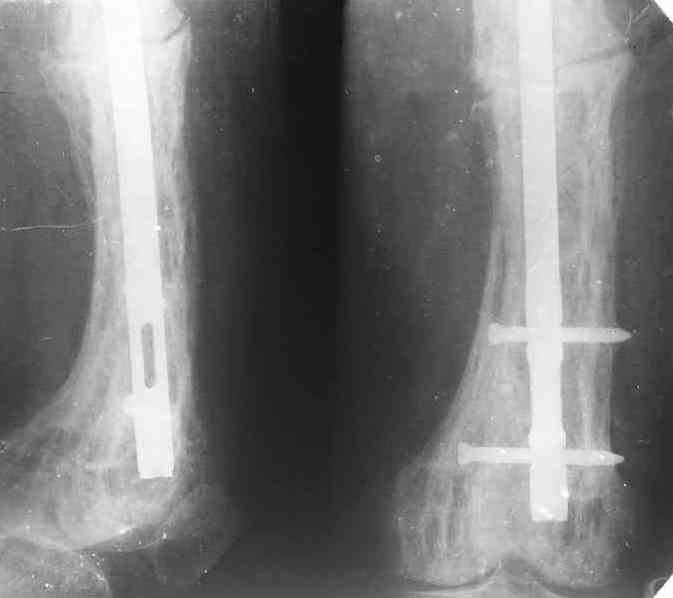

Еще один пример. Пациентка с юга России, прислала рентгенограммы через

год. На сегодня прошло 2 г. 8 мес. после операции. Несмотря на не очень

убедительный процесс сращения, пациентка ходит. Учитывая остеопороз при

Педжете, решили, что динамизировать вообще не нужно.